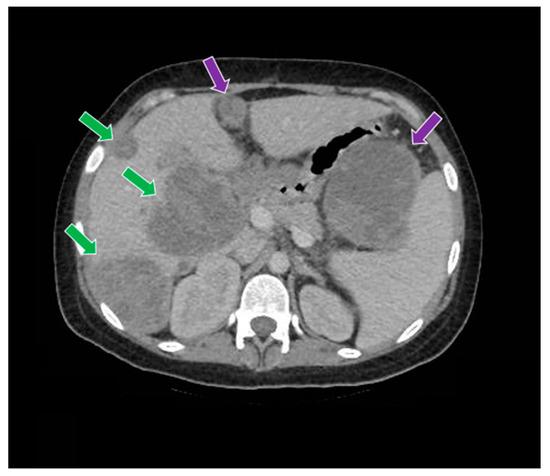

2. Case Report